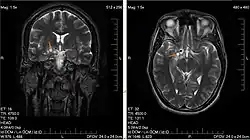

Low-grade brain glioma in a 28-year-old male. (Taken on 10 July 2007)